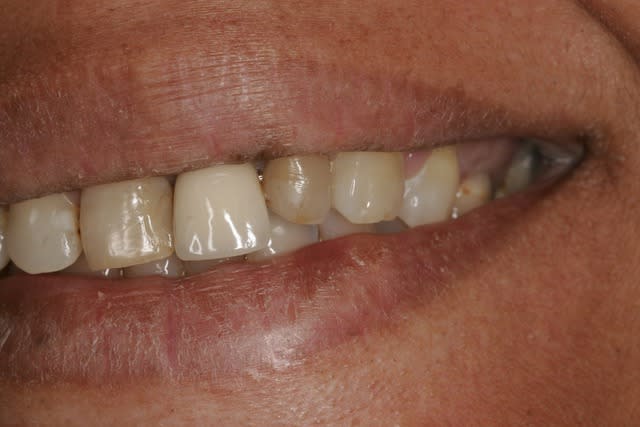

J'ai acheté le Aenial et essayé aujourd'hui sur 3 compos : 11D, 21M, 22M.

J'ai passé du temps même si j'ai pris plus que les SC.

Retour d'expérience avec du Gaenial après quelques cas. Ca tient bien la route, cependant il faut oublier le pinceau silicone qui étale mal ce produit. C'est moins évident de caractériser les bords libres, on obtient une sorte de flou de translucidité entre le transparent TE (opalescent?) et les teintes émail (le plus souvent JE), ce n'est pas aussi net et délimité que chez Micérium, mais l'effet caméléon est cependant plus présent avec le GC ce qui permet d'obtenir un bon résultat plus rapidement. Pour le cas présenté ça donne environ 1H30 pour 2 composites "spot" sur 13 (mésial) et 12 (disto-palatin), 1 composite de bonne taille sur 12 (mésio-vestibulaire), et 2 facettes composite directes sur 11 (vitale), et 22 (dévitalisée), y compris pose/dépose digue, retouche bord libre de la CCM (antédiluvienne), mise en forme et polissage à 90%

Puis 15 minutes de polissage/brillantage 1 semaine après.

Le résultat n'est pas aussi naturel qu'avec le Micérium, mais on est dans du bon niveau tout de même et je pense avoir économisé une bonne heure, avec un peu plus d'expérience et en se défaisant de certains "tics" lié à l'habitude du Enamel HFO, on devrait encore gagner un peu de temps......ça va faire plaisir à la cnsd et à la sécu ça!!!!

Aussi la forme de 12 et 11 semble manquée de volume en vestibulaire

quel amélioration du sourire ! (même si ça ne résout pas tout)

Le montage demande de fixer une zone blanche avec des écarts de teinte et de volume faible, j'y vois mieux à tête reposée plus tard, cela permet aussi de valider la teinte sur un support dentaire non déshydraté .

> Aussi la forme de 12 et 11 semble manquée de volume en vestibulaire

L'idée ici est d'améliorer un sourire et de motiver la patiente à un traitement ultérieur de bonne qualité, elle n'a pas de moyen pour l'instant de reprendre la 21, qui présente une face vestibulaire plate, un manque de soutient de la gencive, et une adaptation radiculaire médiocre, cependant c'est cette 21 qui devient pour l'instant l'élément de référence pour le montage composite, et avec cette vision là, la forme de 11 et 12 est en harmonie (voir même presque trop volumineuse) avec la 21.

Plus tard, dès que ses moyens ( ou sa prise de conscience sur l'état de ses dents et des moyens qui existent pour améliorer la situation) vont le permettre, une proposition esthétique plus global, lui sera proposée et a ce moment là les volumes seront définis par des Mock-up.

On peut "bricoler" avec des composites, cela reste souvent moins délabrant que de la prothèse céramique, mais l'esthétique final et le pronostic sont très souvent moins bon. Je suis persuadé que cette patiente nécessite une prise en charge globale.